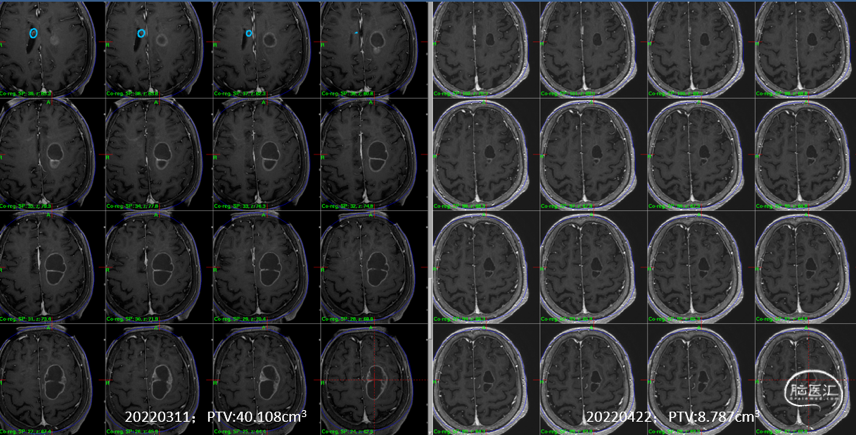

1)左额病灶:囊性病变逐渐缩小

6个月随访时,薄扫增强磁共振(1mm/层)提示肿瘤明显缩小,无放射相关不良反应,没有新发病灶;患者目前仍在规律的随访当中,期待我们的长期随访结果。